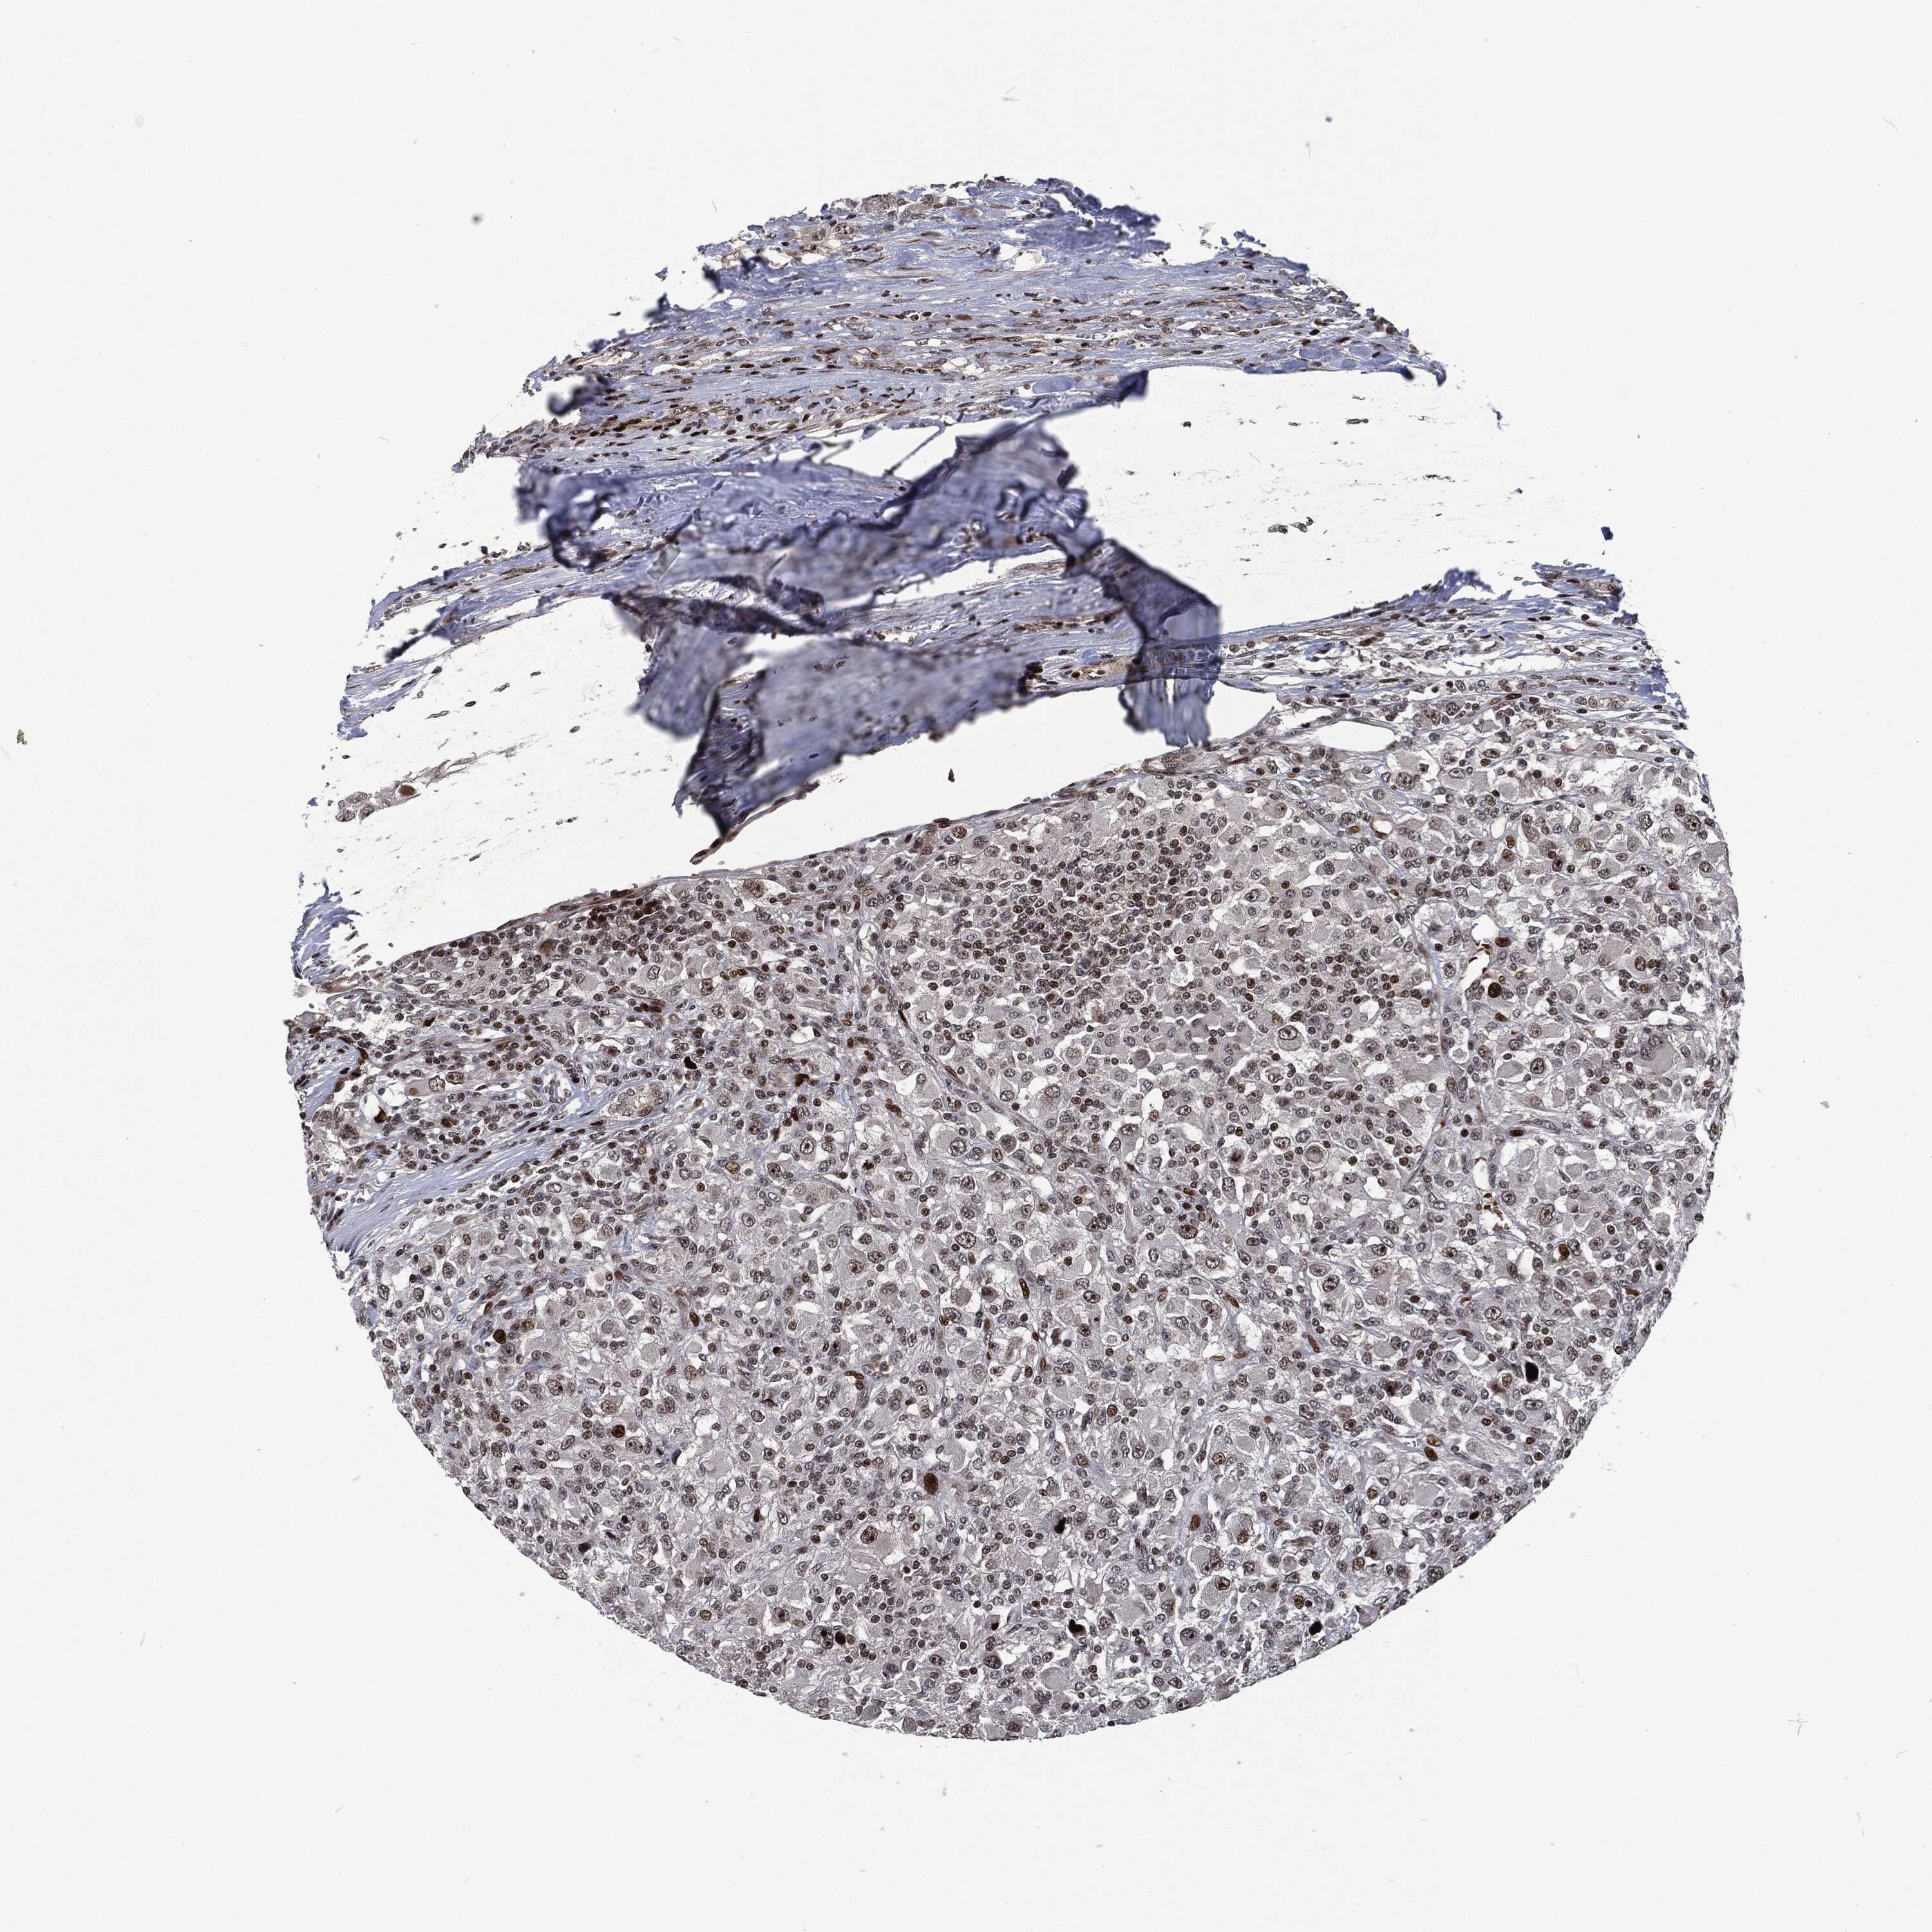

KIDNEY RENAL CLEAR CELL CARCINOMA (VALIDATION) - Interactive survival scatter ploti

The Survival Scatter plot shows the clinical status (i.e. dead or alive) for all individuals in the patient cohort, based on the same data that underlies the corresponding Kaplan-Meier plots. Patients that are alive at last time for follow-up are shown in blue and patients who have died during the study are shown in red.

The x-axis shows the expression levels (FPKM) of the investigated gene in the tumor tissue at the time of diagnosis. The y-axis shows the follow-up time after diagnosis (years). Both axes are complimented with kernel density curves demonstrating the data density over the axes. The top density plot shows the expression levels (FPKM) distribution among dead (red) and alive patients (blue). The right density plot shows the data density of the survived years of dead patients with high and low expression levels respectively, stratified using the cutoff indicated by the vertical dashed line through the Survival Scatter plot. This cutoff is automatically defined based on the FPKM cutoff that minimizes the p-score. The cutoff can be changed by dragging the vertical line or by entering a cutoff value in the square labeled "Current cut-off".

Under the Survival Scatter plot the p-score landscape (black curve; left axis) is shown together with dead median separation (red curve; right axis). Dead median separation is the difference in median mRNA expression between patients who have died with high and low expression, respectively. It is calculated as follows: median FPKM expression of dead patients with high expression - median FPKM expression of dead patients with low expression. This is intended to aid the user in visually exploring custom cutoffs and the associated p-scores and dead median separation.

Individual patient data is displayed and can be filtered by clicking on one or more of the category buttons on the top of the page. Categories describing expression level and patient information include: high, low, alive, dead, female, male and tumor stages. The scale of the x-axis can be toggled between linear and log-scale by clicking on the "x log" button. Mouse-over function shows TCGA ID, patient information and mRNA expression (FPKM) for each patient.

& Survival analysisi

Kaplan-Meier plots summarize results from analysis of correlation between mRNA expression level and patient survival. Patients were divided based on level of expression into one of the two groups "low" (under cut off) or "high" (over cut off). X-axis shows time for survival (years) and y-axis shows the probability of survival, where 1.0 corresponds to 100 percent.

EGFR is not prognostic in Kidney Renal Clear Cell Carcinoma (validation)

Best expression cut offi

Based on the FPKM value of each gene, patients were classified into two groups and association between prognosis (survival) and gene expression (FPKM) was examined. The best expression cut-off refers the FPKM value that yields maximal difference with regard to survival between the two groups at the lowest log-rank P-value. Best expression cut-off was selected based on survival analysis .

When clicking on this number, the vertical dashed line indicating cut-off, the interactive survival plot, and the Kaplan-Meier curve will be adjusted to show results based on the best expression cut-off.

: 44.55

P scorei

Log-rank P value for Kaplan-Meier plot showing results from analysis of correlation between mRNA expression level and patient survival.

N/A

5-year survival highi

5-year survival for patients with higher expression than the expression cutoff.

For melanoma and glioma, 3-year survival is shown.

5-year survival lowi

5-year survival for patients with lower expression than the expression cutoff.

TCGA RNA samplesi

RNA-seq data is reported as average FPKM (number Fragments Per Kilobase of exon per Million reads), generated by the The Cancer Genome Atlas (TCGA) .

Normal distribution across the dataset is visualized with box plots, shown as median and 25th and 75th percentiles. Points are displayed as outliers if they are above or below 1.5 times the interquartile range. FPKM values of the individual samples are presented next to the box plot.

Average pTPM 89.3

Number of samples 100